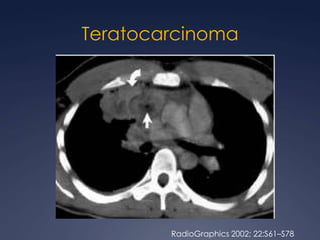

TeratocarcinomaRadioGraphics 2002; 22:S61–S78

25 a 40% de los tumores germinales malignos

90% adultos jóvenes varones